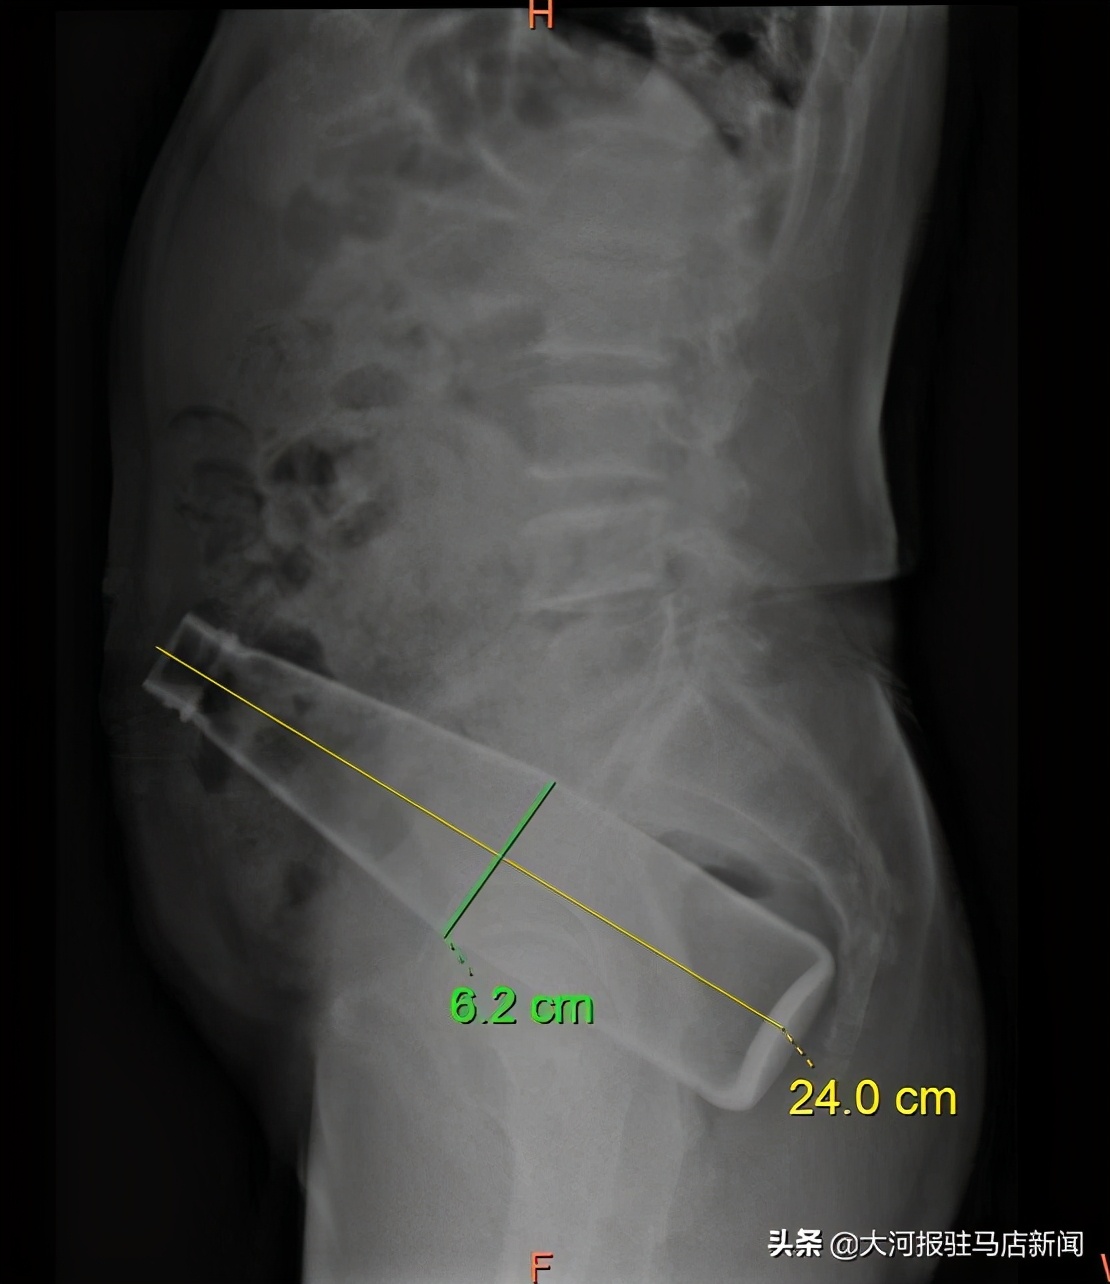

近日,家住驻马店市平舆县的老毕不慎将一个24cm×6cm大小的玻璃瓶塞入肛门,在家中苦苦努力一夜,不但没把玻璃瓶取出,反而导致玻璃瓶越陷越深的情况下,老毕被家人送往驻马店市中心医院肛肠科。

在麻醉科手术部的密切配合下,由团队中手尺寸最小的副主任医师于秀芝自肛门探查玻璃瓶的大概位置,发现玻璃瓶位于直肠乙状结肠交界处,代建德在患者腹部轻柔挤压肠管,将玻璃瓶缓慢推向直肠末端。另一组医生王文航通过肛门撑开器将患者的肛门撑开,触摸到玻璃瓶后,用手术器械将其轻柔地向外牵拉,数名医生上下其手,一起发力,历经一个多小将其成功取出,避免了开腹手术,减轻了患者的创伤。术后第二天,老毕的不适症状明显减轻,术后第三天便顺利康复出院。